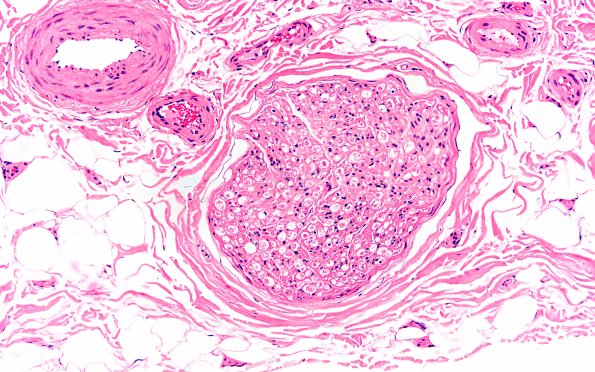

9A2 Axonal Degeneration, fulminant (Case 9) H&E 8

Extensive axonal degeneration is shown. (H&E)